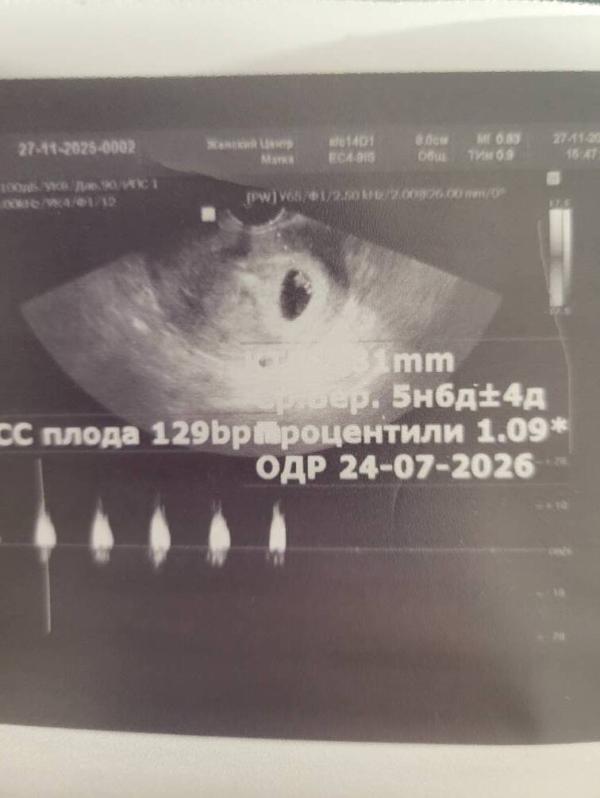

Сегодня была перврм узи ,решила пойти на том же сроке,что и с перврй дочкой,когда у нее услышали сердечко (6 недель и 4 дня)

Первпя фотка и заключение это новая беременрость ,третье фото это моя первая беременность

На сколько отличается ктр и остальные прказатели😭😭😭😭сердцебиение и то на нижней границе нормы(((

По месячным у меня 6 и 4 дня((

Может я и накручиваю себя,просто есть с чем сравнить(сейчас и 3 мм нет,а дочка на этом сроке была почти уже 1 см((